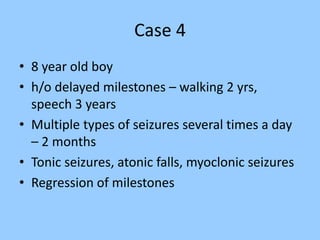

1. The document discusses EEG patterns and findings in various neurological conditions seen in children. It includes descriptions of normal EEG findings as well as abnormal patterns seen in conditions like absence seizures, West syndrome, benign childhood epilepsy with centrotemporal spikes, Lennox-Gastaut syndrome, non-convulsive status epilepticus, subacute sclerosing panencephalitis, and herpes encephalitis.

2. Case studies are presented with clinical histories and EEG findings to illustrate different pathologies. Treatment options are also mentioned for many of the conditions.